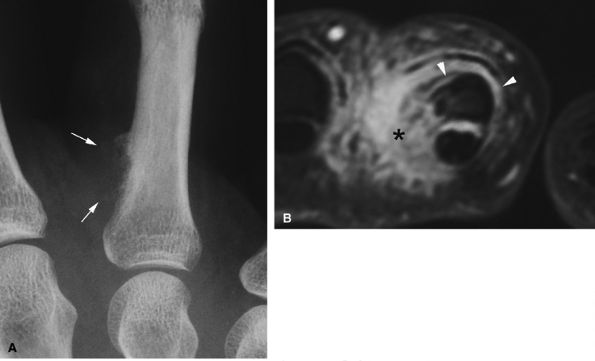

FIGURE 11.73 ● Giant cell tumor of the tendon sheath. Lateral view radiograph shows a large mass of the palmar soft tissue (asterisk) and bone pressure erosion (arrows).

|

seen with synovial sarcomas. Bone and joint invasion is possible.168 Ultrasonography shows a nonspecific solid mass with a variable color Doppler signal. MR images are specific, depicting a well-defined mass with hemosiderin deposits. Typical signal void artifacts are seen on all sequences, particularly on gradient-echo images, and a more heterogeneous and predominantly low signal is found on T2-weighted images.162,166,169 The lesion typically enhances after intravenous injection of gadolinium (Fig. 11.74). The tendon sheath of the flexor digitorum tendons is usually partially or totally enveloped; the extensor tendons are less commonly involved. Some lesions may be more aggressive, and diffuse lesions are seen in multiple locations with invasion of both the flexor and extensor tendons (Fig. 11.75).170